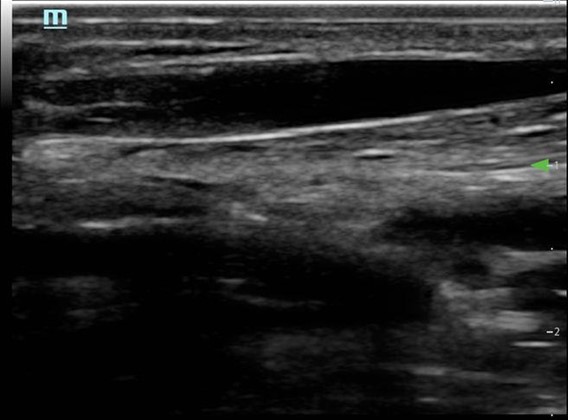

- Needle and vessel kept in the same plane (Fig. 6)

Figure 6. Long axis approach: Vessel appearance